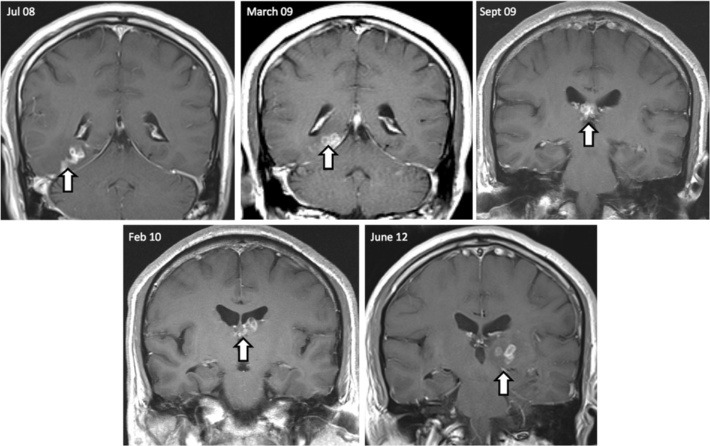

症例は50歳男性。主訴は頭痛およびてんかん発作など。英国在住の中華系で、しばしば故国と行き来をしていた。さしあたってMRIを見るのが手っ取り早い。5枚の前額断MRIの期間は四年間である。白矢印で指されているのが虫体である。症状として、嗅覚異常や記憶のフラッシュバックも起きたらしい。それなんてひぐらし?

病理学的には壊死を伴う肉芽腫性炎症を呈するらしい。

なお、生検で採取された虫体には、口器(mouth parts)や小鉤(hooklets)は含まれていなかったとのこと。つまり、放置していると、またゴソゴソ這い回る可能性がある。患者はalbendazoleを投与され全身状態は良好らしいが、エスカゾール錠の添付文書を見てみると、「海外において、脳を寄生部位とする有鉤嚢虫症患者に本剤を使用した場合、脳内の死滅虫体による炎症性反応の結果として、けいれん発作、頭蓋内圧上昇及び局所神経徴候等の神経症状が発現し、死亡に至ったとの報告がある」との記載もあり、おちおち安心してもいられない。